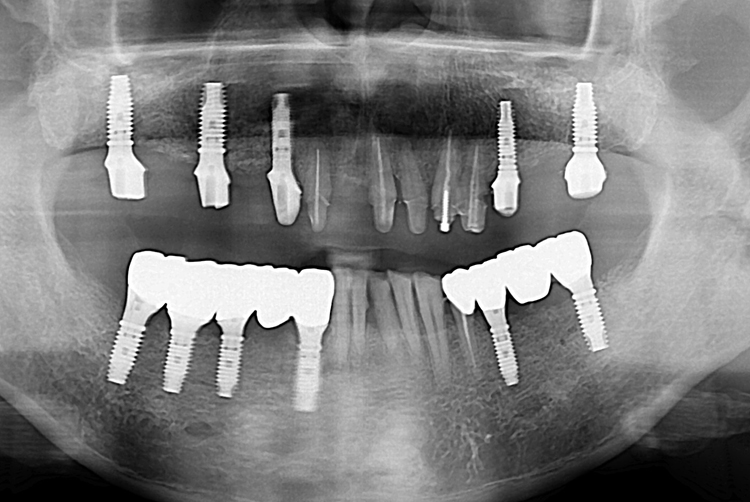

[임플란트] 전체 임플란트

치료후 : 2019-07-05

세종치과는 많은 환자와 다양한 케이스를 바탕으로

항상 편안한 임플란트 수술을 제공하고자 노력하고,

오래동안 튼튼히 쓸 수 있는 임플란트 수술을 가장 큰 목표로 삼고 있습니다.